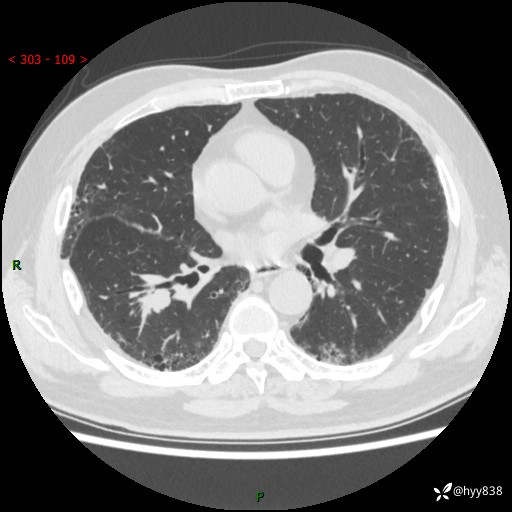

71岁/男,咳嗽伴气促半月。一年前肺手术史,又见两个结节,穿刺结果意外---结果公布~

【现病史】:患者半月前无明显诱因出现咳嗽、咳痰,为白色粘痰,无明显加重与缓解因素,伴气促,无发热,无大量脓痰,无胸痛、咯血,无哮鸣音,到我院就诊,胸部CT示右肺结节增大,并口服药物治疗无明显好转,具体用药不详,为求进一步治疗随来我院,经门诊以“孤立性肺结节”收入我科。 病程中患者精神、饮食可,睡眠不佳,大小便正常,体力下降,体重未见明显下降。

[既往史]:2022-06于当地第一人民医院确诊慢阻肺,现规律使用杰润(1次/日);2023-04-06于当地市第一人民医院行胸腔镜右肺上叶楔形切除术+右肺上叶切除术+淋巴结清扫术+胸膜黏连松解术,确诊为右肺鳞癌 pT2aN0M0 Ib期

【检查】:胸部CT平扫+增强